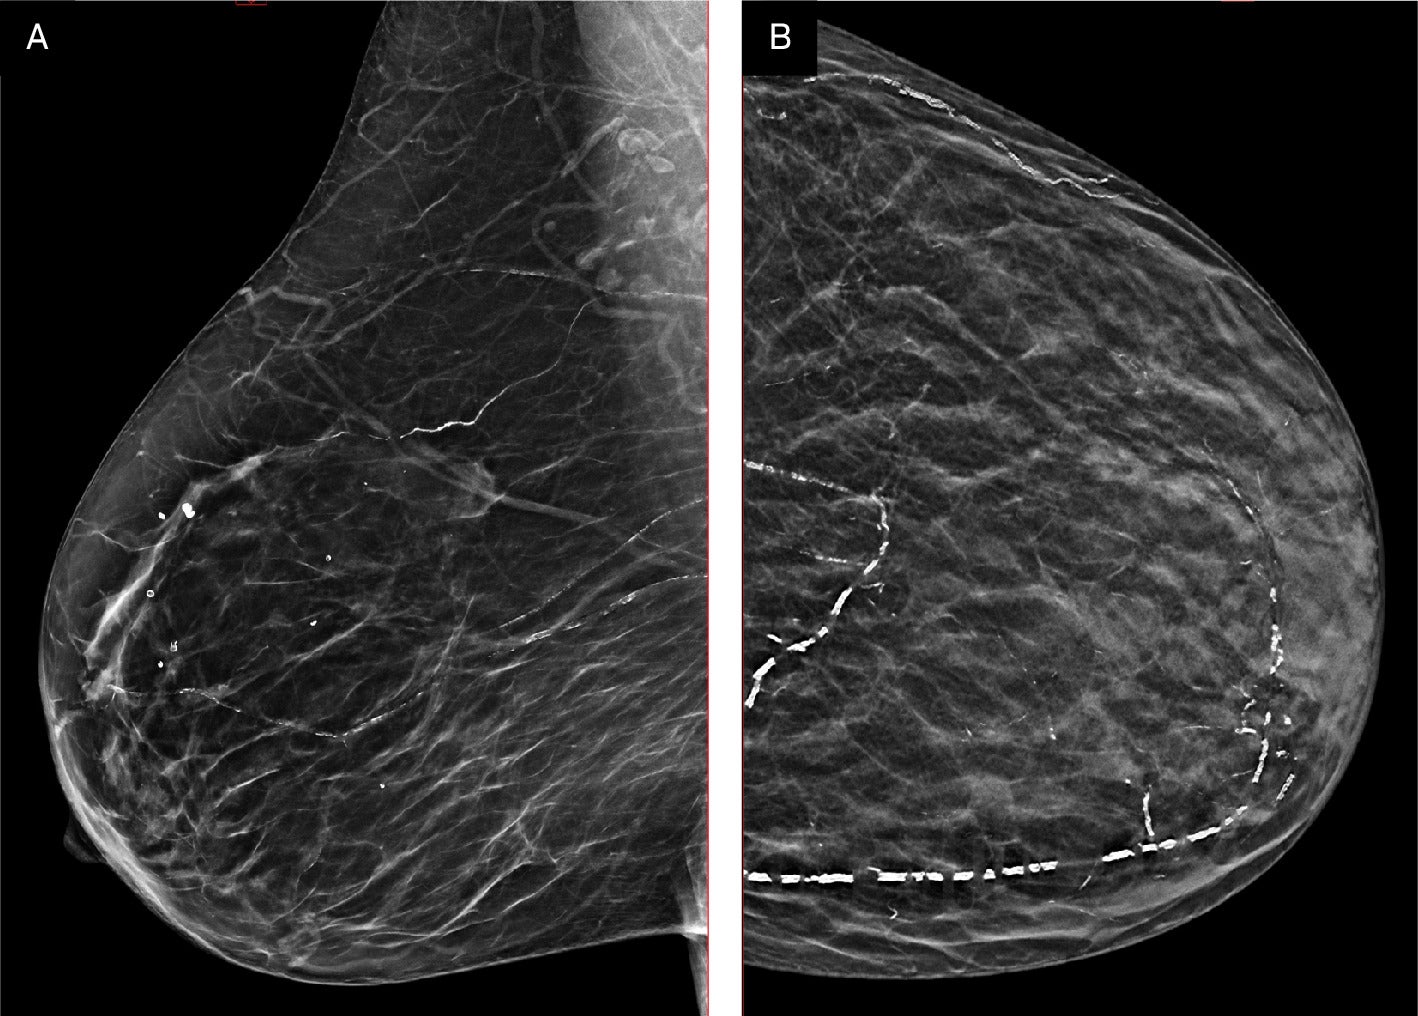

Breast arterial calcification (BAC) has long been visible to radiologists reading mammograms. It appears as characteristic linear, parallel “tram-track” calcifications outlining breast arteries1 —easy to spot, easy to classify, and entirely incidental to the task at hand: ruling out breast cancer. Because BAC is not a marker of breast malignancy, however, radiologists have historically ignored it in reports, dismissing it as a benign finding.

Right MLO (A) and left CC (B) views of a breast with Grade 3 breast arterial calcification. Images courtesy Canadian Society of Breast Imaging.